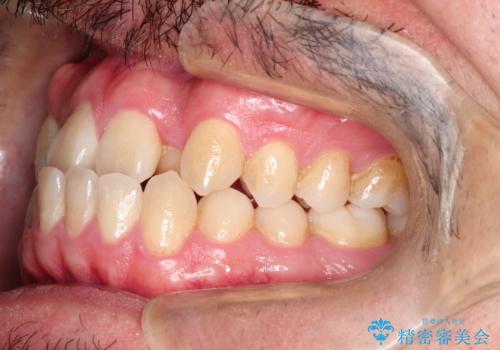

前歯が反対にかんでいる インビザラインとワイヤーを組み合わせた矯正治療

- 前歯が正常とは反対にかんでいるとのことで、来院されました。